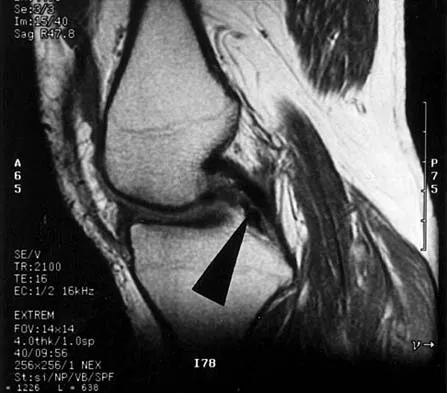

A 48-year-old man has recurrent right knee pain. Figure 52a shows the sagittal proton density T2-weighted MRI scan, and Figure 52b shows the sagittal T2-weighted MRI scan at the same level. The arrow is pointing to a

Explanation